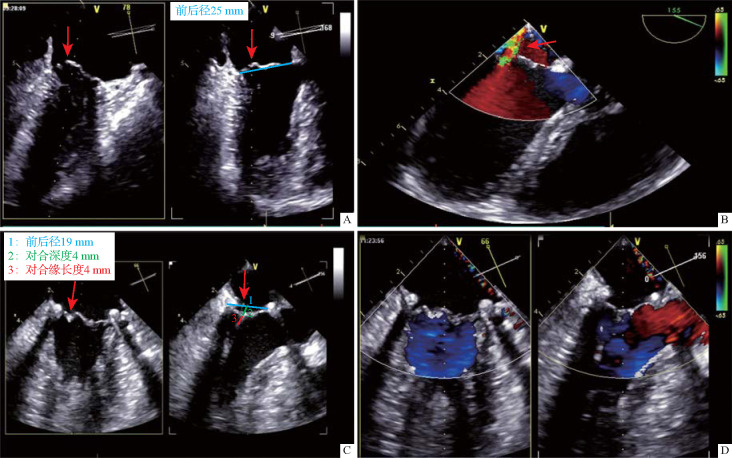

Methods: The study group comprised of thirty-two adult patients with atrial septal defect who underwent thoracoscopic repair surgery at the First Affiliated Hospital of the Air Force Medical University from March to September 2022. Two-dimensional and real-time three-dimensional transesophageal ultrasonography of the mitral valve were performed after anesthesia. The parameters of the mitral valve structure at the late diastolic and late systolic stages were recorded, including anteroposterior and left-right annular diameters, anterior and posterior valves lengths, the vertical distance from the coaptation point of leaflet zone 2 during systole to the annular plane (mitral valve coaptation depth) and mitral valve coaptation length. Data from 32 patients with normal intracardiac structure and no mitral valve regurgitation (control group) were also collected and compared with those of the study group. Concurrent mitral valvoplasty was performed during the atrial septal defect repair surgery for 7 patients with significant mitral valve structural abnormalities and 2 patients with significantly increased mitral regurgitation after cardiac resuscitation. The study group was followed up with transthoracic echocardiography for 2 years postoperatively.

Results: In the study group, 26 (81.3%) patients had varying degrees of mitral valve morphological abnormalities. Among them, 10 (31.3%) patients had short mitral valve coaptation length or depth, 12 (37.5%) patients had closure point malposition, and 4 (12.5%) patients had different bulge of anterior and posterior leaflets. Compared with the control group, the study group had significantly smaller systolic and diastolic mitral left-right annular diameter, mitral posterior valves lengths, mitral coaptation length or depth (all P<0.05), a higher pulmonary systemic flow ratio (P<0.01), and a lower maximum blood flow velocity across the mitral valve (P<0.05). After 2 years of follow-up, among the 9 patients who underwent concurrent mitral valvoplasty, the mitral valve maintained no or little regurgitation, and the average mitral valve pressure difference was less than 5 mmHg (1 mmHg=0.133 kPa). Among the 23 patients without concurrent mitral valvoplasty, 2 patients had moderate regurgitation 1 year after surgery, with a pulmonary/systemic flow ratio larger than 2.8.

目的:探讨经食管超声心动图评价二尖瓣在房间隔缺损修复术中的应用。方法:收集2022年3月至9月在空军军医大学第一附属医院行胸腔镜下房间隔缺损修补术的成人患者32例(研究组)。麻醉后行经食管二尖瓣二维及实时三维超声检查。记录舒张晚期和收缩期二尖瓣结构参数,包括前后、左右环直径、前后瓣长度、收缩期小叶2区吻合点到环平面的垂直距离(二尖瓣吻合深度)、二尖瓣吻合长度。同时收集32例心内结构正常、无二尖瓣返流的患者(对照组)的上述数据,并与研究组进行比较。对7例二尖瓣结构明显异常及2例心脏复苏后二尖瓣返流明显加重的患者在房间隔缺损修复术中行同期二尖瓣成形术。术后随访2年经胸超声心动图。结果:研究组有26例(81.3%)患者有不同程度的二尖瓣形态异常,其中10例(31.3%)患者二尖瓣闭合长度或闭合深度短,12例(37.5%)患者有闭合点错位,4例(12.5%)患者有前后小叶不同程度的凸出。与对照组相比,研究组的收缩期和舒张期二尖瓣左右环直径、二尖瓣后瓣长度、二尖瓣覆盖长度或覆盖深度均明显小于对照组(均为ppp)。房间隔缺损较大的患者常合并二尖瓣结构异常,术中建议经食管超声心动图对二尖瓣进行评估,如有明显的二尖瓣结构异常,可同时行二尖瓣成形术。